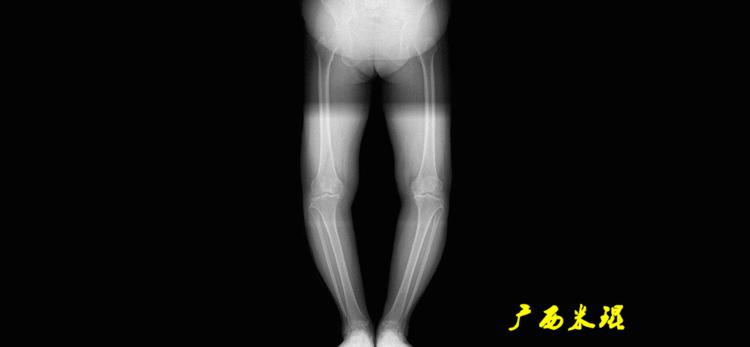

最常见的下肢畸形发生于冠状面,即膝内外翻畸形,冠状面的对线异常通过应用“对线异常检验”进行分析,机械轴的偏移(MAD)表现为对线异常。

膝内翻是指下肢力线通过膝关节中心点内侧,距中点2mm以上,偏内超过15mm为显著膝内翻。膝外翻是指下肢力线通过膝关节中心点外侧,距中点2mm以上,偏外超过10mm为显著膝外翻。

解剖胫骨近端外侧角(也叫aMPTA):胫骨干上段轴线与胫骨平台切线(关节线)在膝关节外侧所形成的夹角,常称为胫骨角,正常为87°±3°。大多数膝内翻患者的畸形发生于胫骨上端,表现为胫骨角大于90°。严重的膝内翻畸形发生在整个下肢,股骨干及胫骨干都有可能形成向内弯曲的弧形。